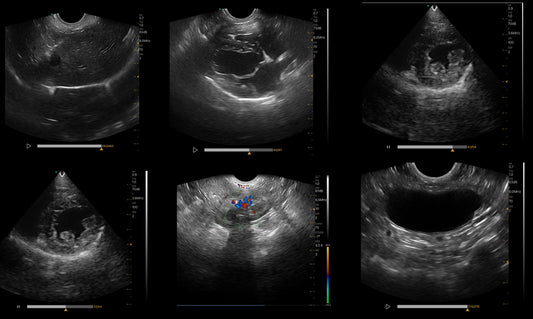

Canine abdominal ultrasound provides a detailed view of the organs and structures within the abdomen. It is a non-invasive diagnostic tool that veterinarians use to evaluate a variety of conditions...